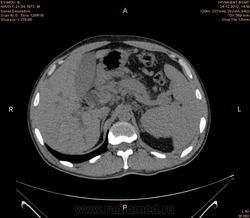

Предварительно образование головки ПЖ, и в печени. Что с ферментами?

на операций рак головки подж.железы с метастазир. печень.

инфильтрация тут нисходящей 12 перст кишки , расширенного холедох,расширенный вирсунгов проток ,нижная граница очень близко прилежит к нижней полой вене с правой почечной веной ,но четко визуализирутся передний листок фасции Героты(нельзя исключить ее инфильтрацию), инфильтрация конгломератом увеличенных лимфатических узлов ворот печени портальной вены с варикозным расширением вен, на вышележащий срезах четко определяются верхняя брыжеечная вена и артерия ,не хватает срезов для полной визуализации(помогли бы мпр),инфильтрирована восходящая ободочная кишка,конгломерат лимфат узлов за головкой поджелудочной железы в виде гиподенсивного участка вытянутой формы , ,мтс в печень,парааортальные